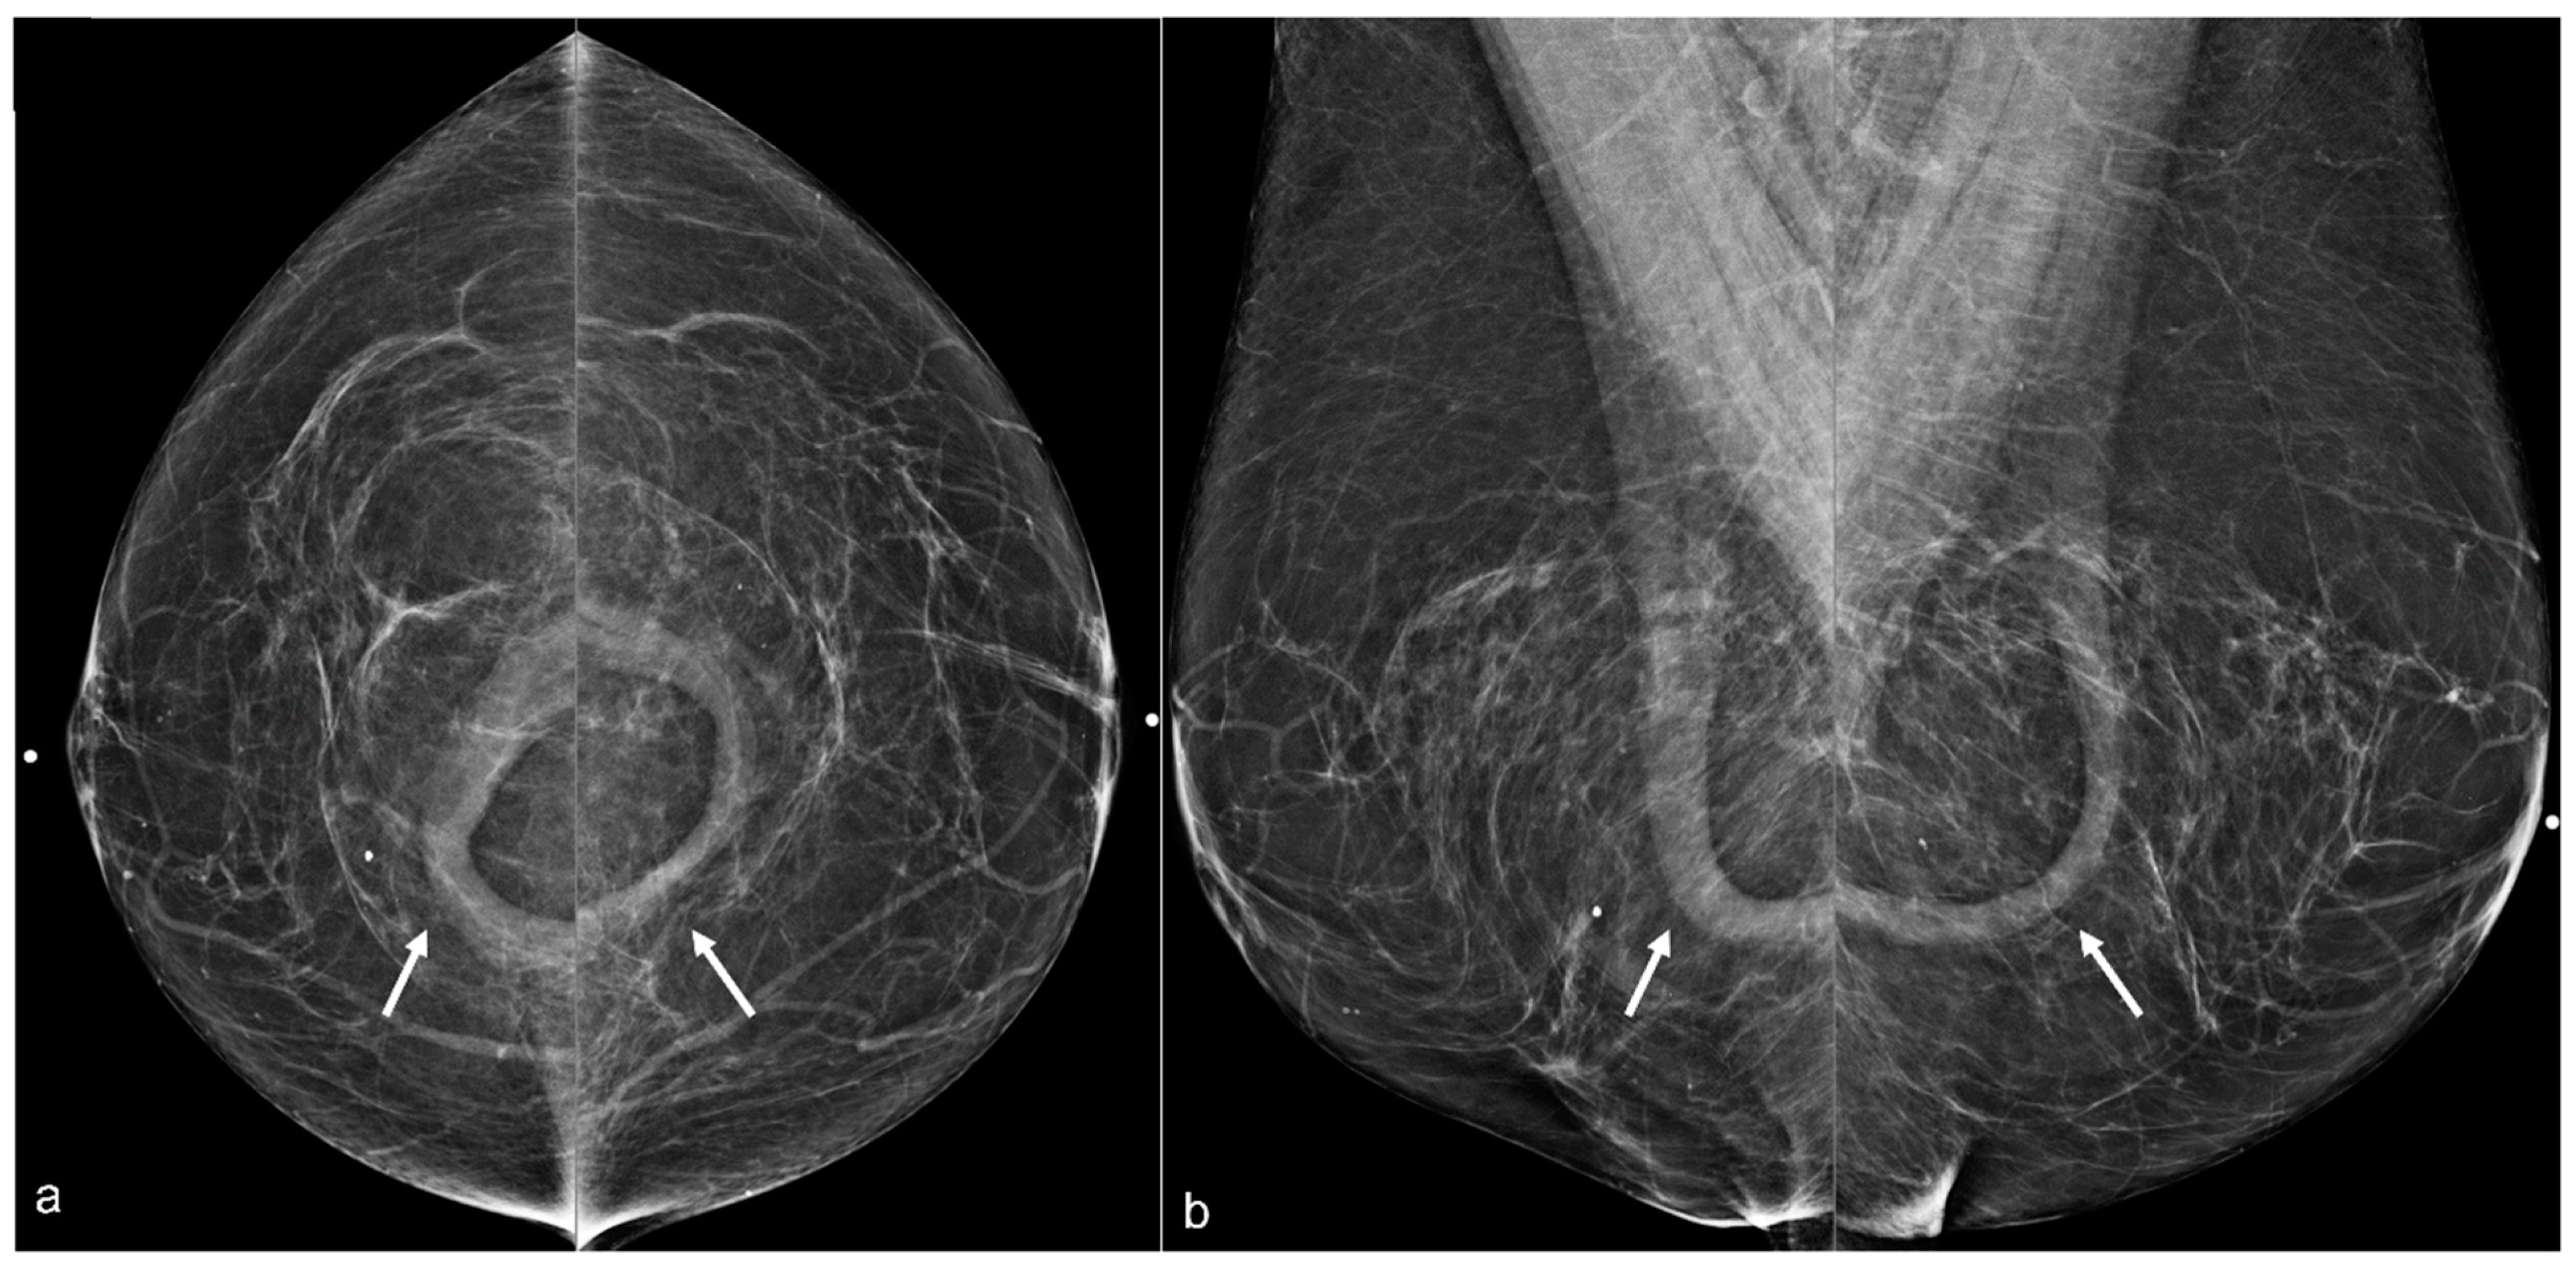

Figure 11. A 67-year-old woman with a history of subglandular silicone implants. Mammograms with bilateral CC (a) and MLO (b) views demonstrate curvilinear densities (arrows), consistent with residual implant capsules.